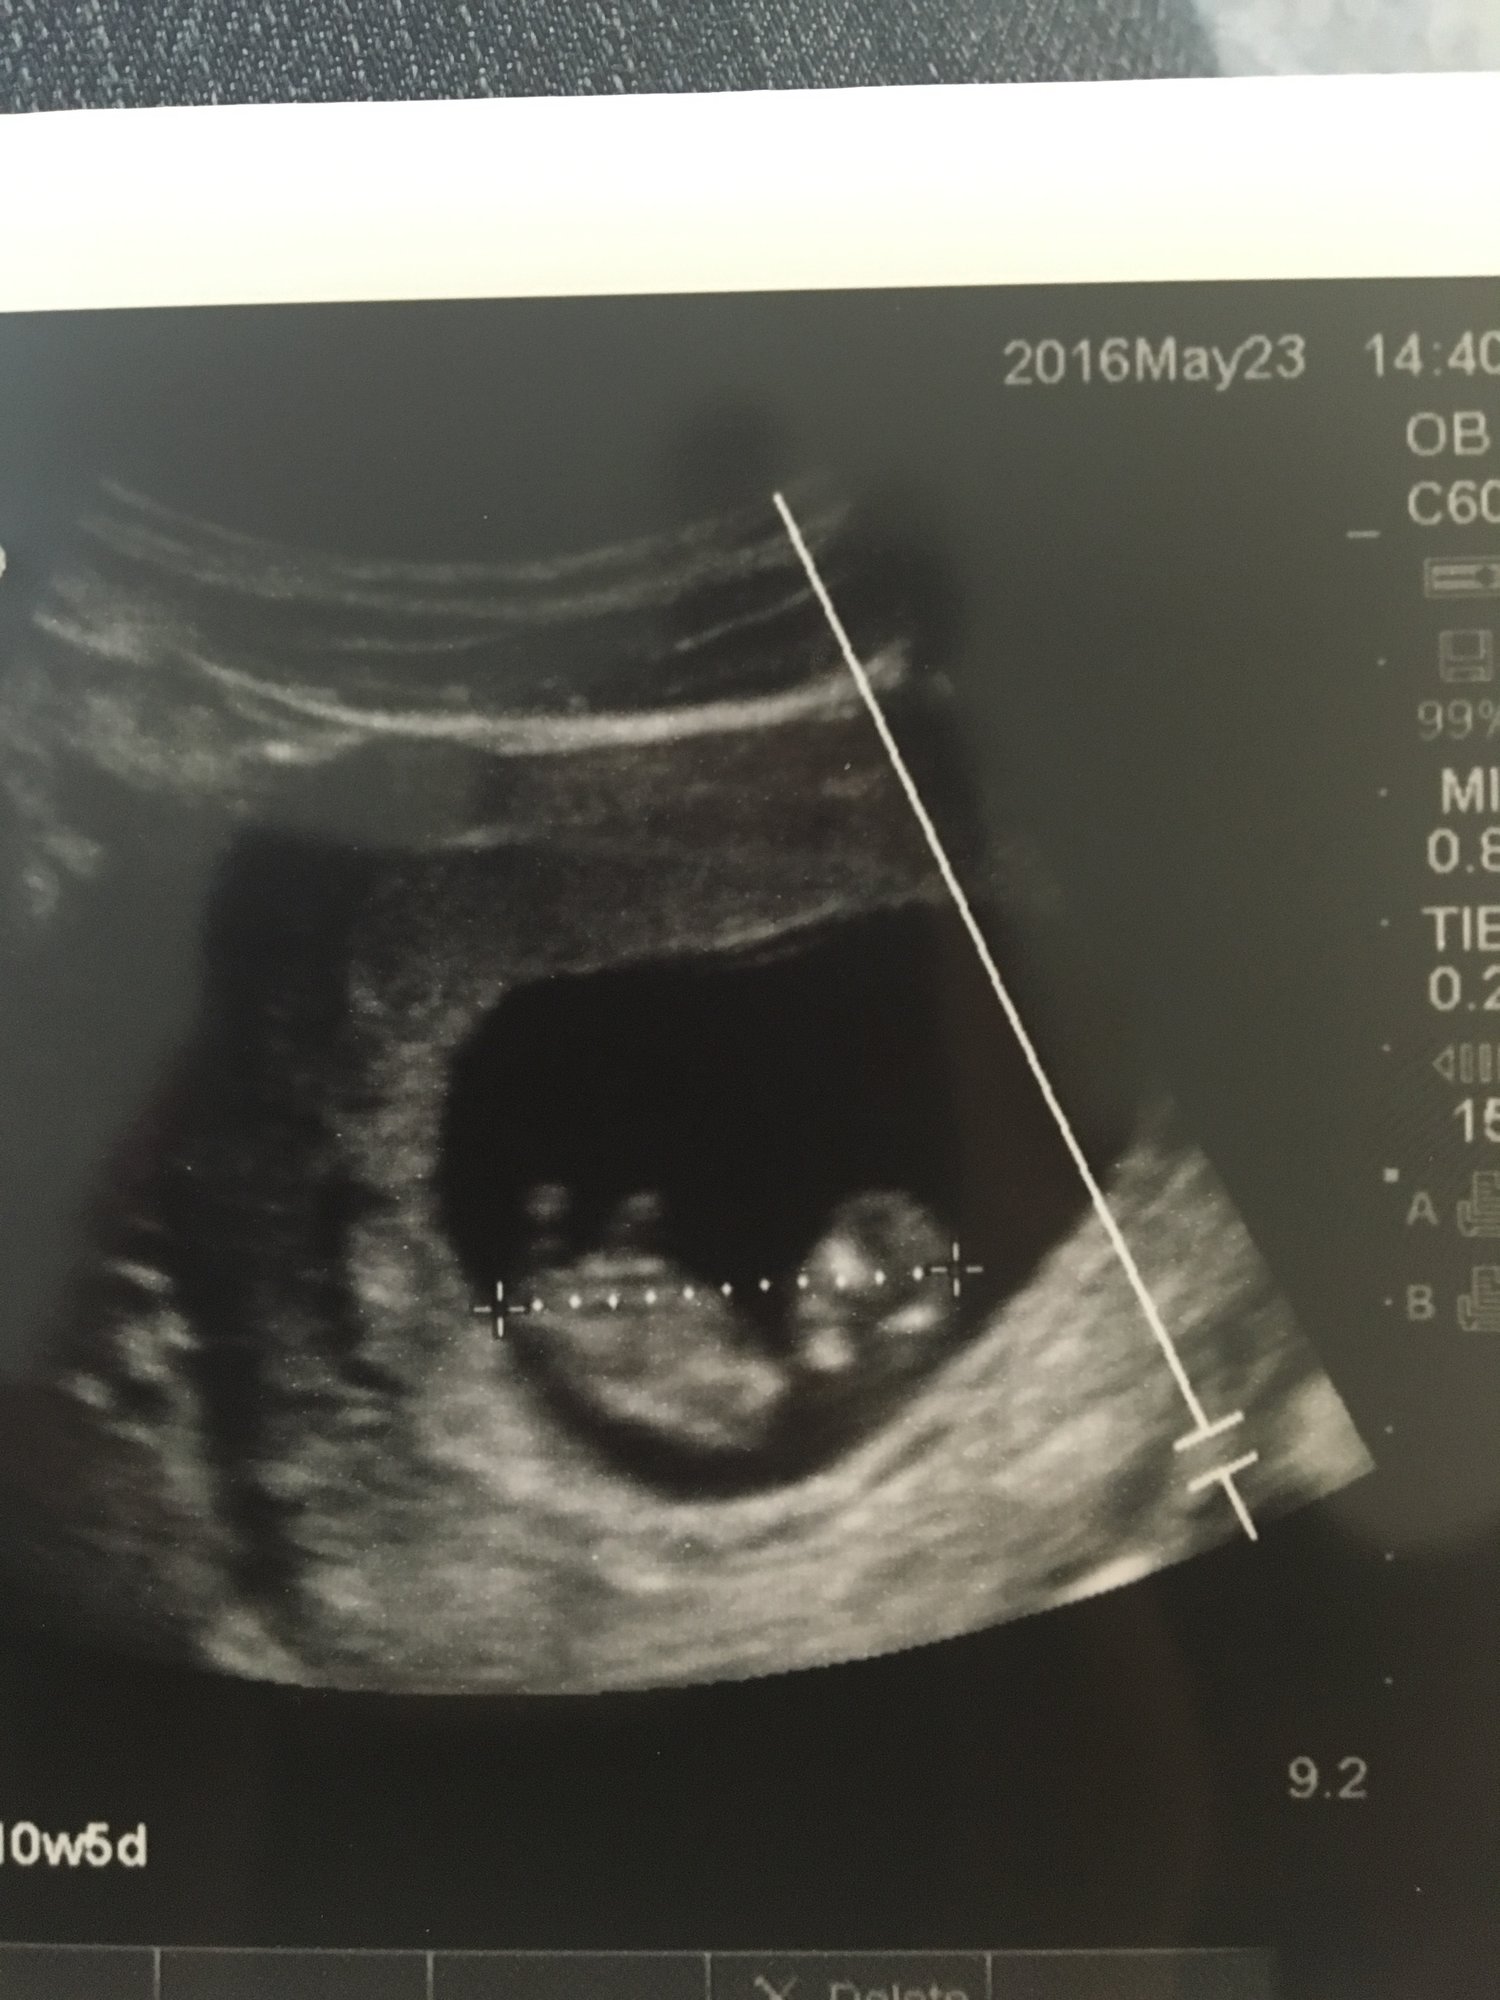

I've been reading about the "nub theory" and am curious as to how it works or what exactly you're supposed to be looking for. This is our first, so I'm a little new to all of this. Any help is appreciated. I also posted our 11 week ultrasound to get anyone's thoughts and opinions. Thanks Mom's. ❤️

• I've heard that nub theory only works after 12 weeks. The only things I'm seeing on yours are baby's feet and a bright white spot that I'm guessing is the umbilical cord. There is a nub there because all babies have one but baby is way too tiny at this point to see it.

• Yeah I wouldn't know how to tell about the nub either way but I agree the baby is way too small and also not facing the right way.  Our NT scan was at 11w 4d and we couldn't make out a nub at all.